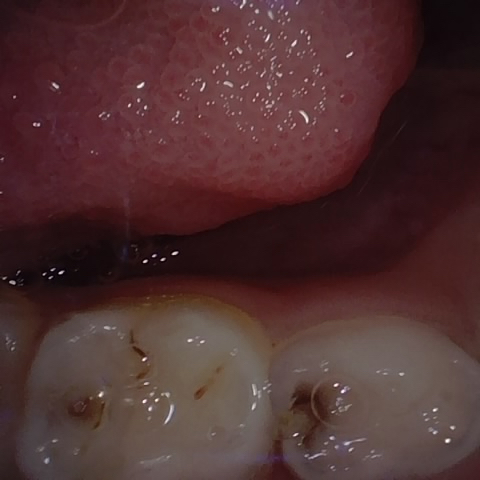

Annotated as "Good"